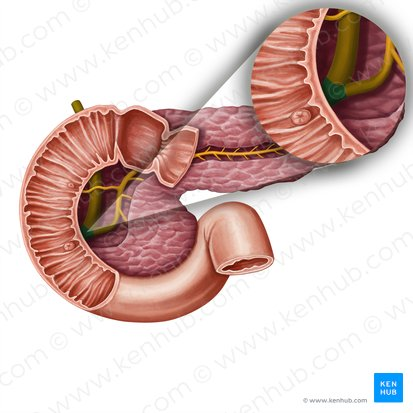

Duodenum

This is the first and shortest segment of the small intestine. It receives partially digested food (known as chyme).

Receives digestive enzymes from the pancreas and bile from the liver and gallbladder through the pancreatic and bile ducts.

Pancreatic Duct

A duct that carries digestive enzymes produced by the pancreas to the duodenum. It typically joins with the bile duct before entering the duodenum.

Bile duct

A duct that carries bile produced by the liver and stored in the gallbladder to the duodenum, where it aids in the digestion of fats.

Major Duodenal Papilla

An opening in the wall of the duodenum where the common bile duct and the pancreatic duct typically enter to deliver bile and pancreatic enzymes.

Pancreatic Duct / Duct of Wirsung

The main duct that runs through the length of the pancreas, collecting digestive enzymes from the pancreatic cells and transporting them to the duodenum.

Accessory Pancreatic Duct / Duct of Santorini

A smaller pancreatic duct that branches off the main pancreatic duct and may also empty into the duodenum, usually superior to the major duodenal papilla.

Hepatopancreatic Ampulla / Ampulla of Vater

A dilated chamber formed by the joining of the common bile duct and the pancreatic duct before they enter the duodenum.

Sphincter of Hepatopancreatic Ampulla / Sphincter of Oddi

A muscular valve that surrounds the hepatopancreatic ampulla and controls the flow of bile and pancreatic juice into the duodenum.

Major Duodenal Papilla

The raised opening in the wall of the duodenum where the hepatopancreatic ampulla typically empties its contents.

Mucosa of Duodenum

The inner lining of the duodenum, which contains specialized cells for absorption and secretion.